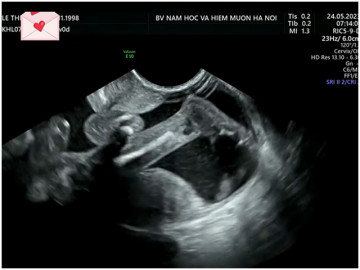

Mẹ bầu 38 tuổi làm thụ tinh ống nghiệm và mang song thai 2 bánh rau 2 buồng ối. Vào thời điểm khi thai được 12 tuần, mẹ bầu này đã đến viện khám sàng lọc. Qua thăm khám, bác sĩ Sơn ghi nhận 1 thai có độ mờ da gáy bình thường 1mm, nhưng 1 thai có độ mờ da gáy dày 5.5mm đi kèm với bất sản ống tĩnh mạch.

Ở thời điểm 3 tháng, 2 bé phát triển ổn định. (Ảnh: BSCC)

Được biết, mẹ bầu 38 tuổi này đã được mổ lấy thai ở tuần thứ 37. Hai em bé sinh ra khoẻ mạnh với cân nặng đều 2,5kg. Hiện tại ở thời điểm 3 tháng, 2 bé phát triển ổn định.